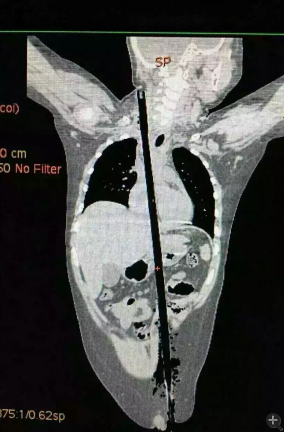

據(jù)相關(guān)知情人介紹,受傷男童24日晚在家中與小朋友一塊兒在墻頭上玩耍時,一不小心從高墻上跌落到了鄰家花圃中,讓人觸目驚心的是,該男童正好跌到了花圃中的一支長約63厘米,直徑約1.5厘米的竹棍上,竹棍自孩子的左側(cè)大腿根部直接插入腹腔并入胸腔直至右側(cè)頸部。

市兒童醫(yī)院組織專家團(tuán)隊(duì)對孩子的病情進(jìn)行檢查、評估后發(fā)現(xiàn),竹棍由患兒左側(cè)大腿根部插入,經(jīng)腹腔穿透胃、肝臟、膈肌入胸腔,并穿透患兒心臟,經(jīng)胸腔入頸部,此刻不能拔除竹棍,因?yàn)槿コ窆鲿䦟?dǎo)致心臟、肝臟破裂大出血導(dǎo)致休克,危及性命。

由于竹棍自心臟的右心房膈面穿入心臟,并由右房近左房頂處穿出心臟,經(jīng)右胸頂刺入右頸部,右心房破口處緊鄰右冠狀動脈,幸運(yùn)的是胸腔內(nèi)大血管無損傷,在體外循環(huán)輔助下,醫(yī)護(hù)團(tuán)隊(duì)異物穿出處鋸斷異物,將插入心臟內(nèi)的竹棍截?cái)喟纬扪a(bǔ)心臟破損處,向上繼續(xù)尋找周圍組織的游離異物,見異物緊臨頸部大血管,經(jīng)精細(xì)手術(shù),終于抽出了異物。整個手術(shù)時間花了十多個小時。